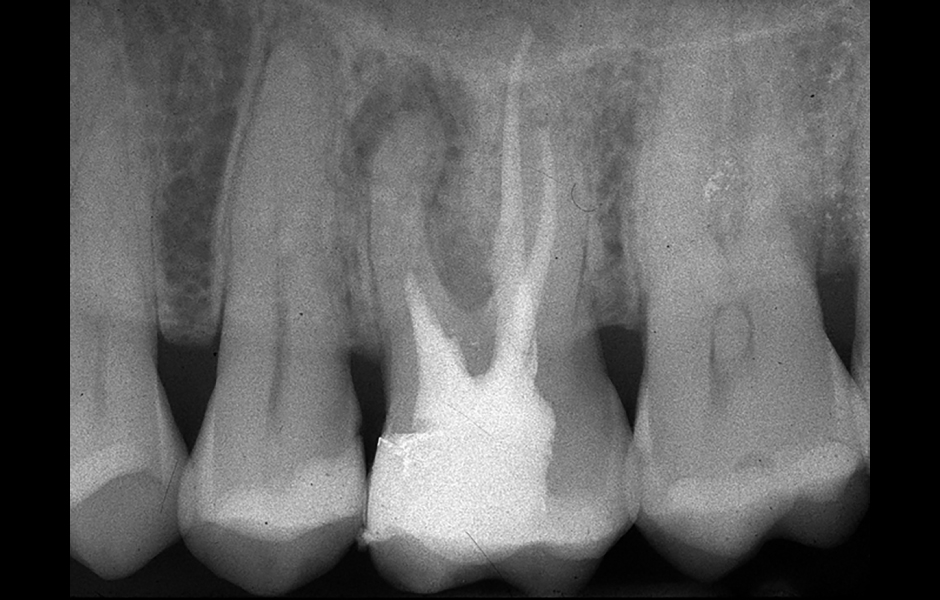

Obr. 4.1: Předoperační snímek horního levého prvního moláru. Oba kanálky mesiobukálního kořene byly kompletně kalcifikované a nebylo možné je ortográdně zprůchodnit.

Obr. 4.3: Retrográdní výplň MB1, MB2 a isthmu.

Obr. 4.4: Pooperační rentgenový snímek zobrazující retrográdní výplň z bílého MTA.